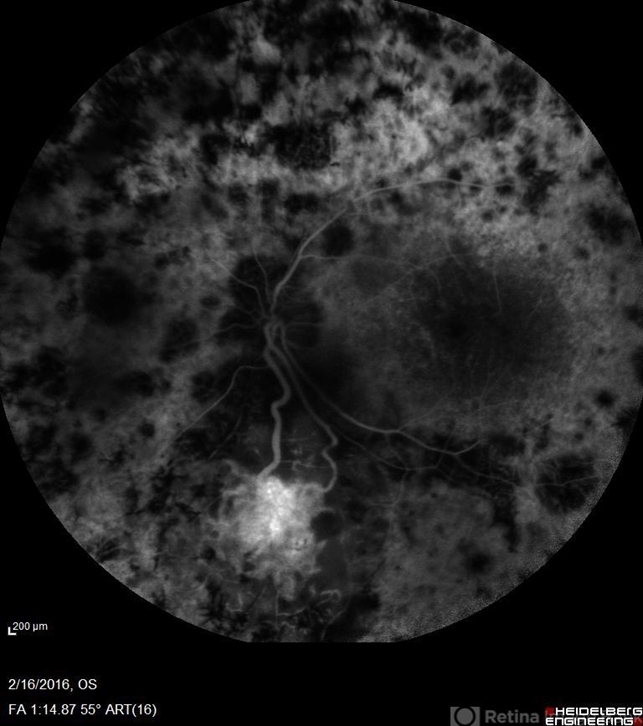

- retinitis pigmentosa, hemangioma

- Imaging device

- Scanning laser ophthalmoscope

- Fluorescein angiography OS of a patient having retinitis pigmentosa with a hemangioma inferiorly.